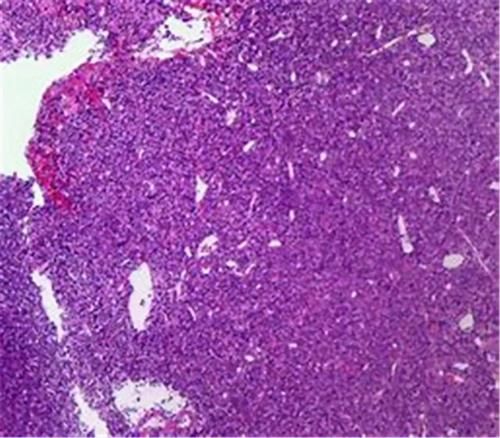

肿瘤是人体在致瘤因子的互相作用下,于人体局部组织细胞曾生出来的新生物,这种新生物一般呈现突起的模样,也被叫做赘生物。

肿瘤组织的细胞形态和组织结构,都和普通的正常组织不同,但是这类异型性肿瘤之间有良、恶之分。其中,异型性较小,这说明分化程度高,这是恶性肿瘤的主要依据来源;异型性较大,这说明分化程度低,这是良性肿瘤的主要依据来源。恶性肿瘤要比良性肿瘤有较为明显的异型性。